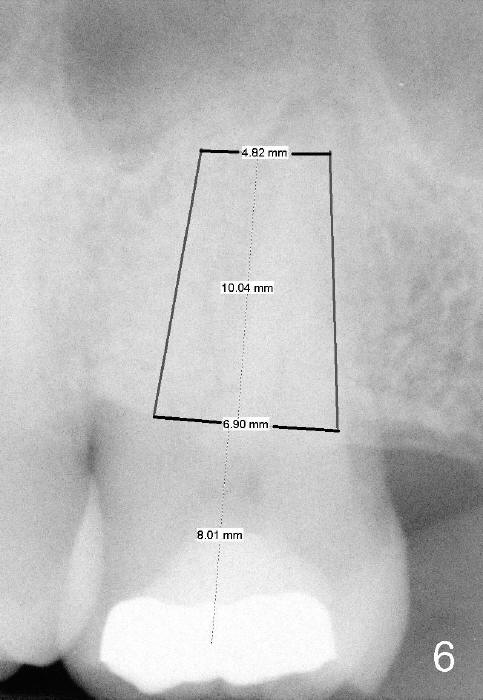

A 52-year-old black man fails to return to finish root canal therapy for the tooth #15; ultimately it is non-salvageable (Fig.1-3). The tooth has 3 basically fused roots (Fig.4 black (buccal) and red (palatal) outlines), above which is the sinus septum (*). By inserting an immediate implant into the sinus septum, primary stability should be high (Fig.5 vs. 6).